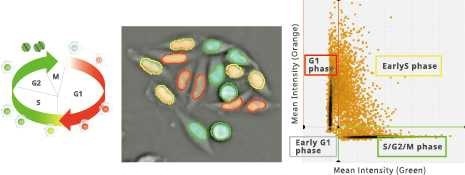

Classification of cell cycle (G1, Early S, SG2M) using the Fucci system

- Added 0-6.8 μM etoposide to HeLa cells using Fucci

- 48-hour time lapse over 1-hour intervals at 10×; 488 nm and 561 nm

6.8 μM Etoposide. Image Credit: Yokogawa Life Science

Control. Image Credit: Yokogawa Life Science

Ratio of cells in each cell cycle at each well. Image Credit: Yokogawa Life Science